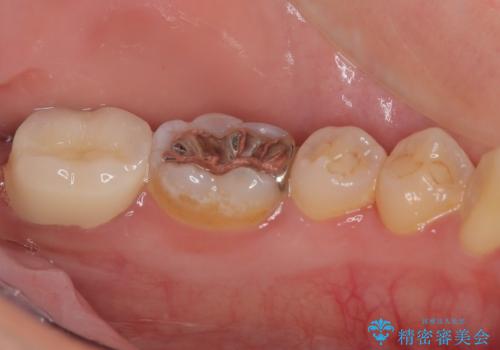

- 過去の歯医者通いの恐怖から虫歯を放置してきたものの、一大決心して来院された患者様です。

神経組織の失活している歯や歯根だけが残っている歯などがあり、全体的に歯石も多く付着している状態でした。

その後、歯根だけとなっている歯はインプラントに、神経組織の失活している歯は根管治療を行い、いずれもオールセラミッククラウンにて補綴治療を行うこととしました。